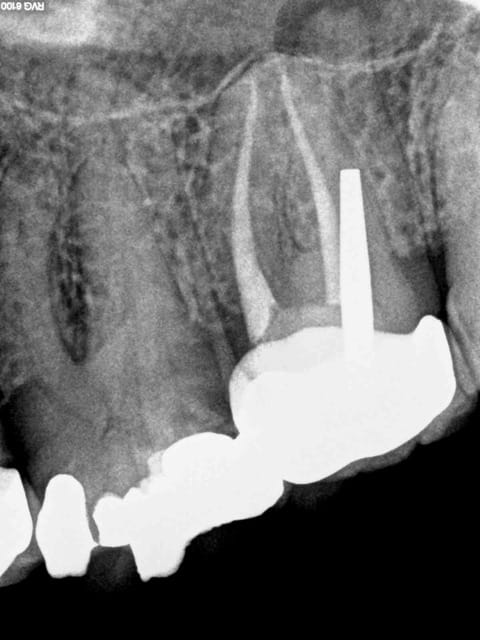

bon attend je vais chercher mes lunettes ,par ce que je ne vois rien de si mediocre au niveau endo . de quelle radio parles tu ? on parle bien de la 2 eme au milieu ?

La plus claire pour moi est la troisième tout à droite, la gutta ne disparaissant pas j'en déduis que l'obturaton sur la deuxième est constituée essentiellement, sinon exclusivement de ciment, je te fais la même en 10 minutes, tire nerfs lentulo pâte, un cône accessoire histoire de en distal.

Je suppose aussi qu'il s'agit de la radio preop du dentiste suivant et qu'il n'a pas encore déposé.

C'est quand-même dommage d'arriver à l'apex et d'obturer avec un matériau résorbable, non? Objectivement cette endo à trois ans est pourrie. La post-op ok il y a du matériau radio opaque à l'apex, mais celle avec la couronne... J'ai le souvenir d'un étudiant qui à la fac fabriquait le ciment d'obturation en mettant de l'eau distillée au lieu de l'eugénol. Pas cool.

question con surement mais en distal il y a avait un cone de gutta

il est passé ou sur l'image N°3

ca disparait pas ce genre de truc....normalement